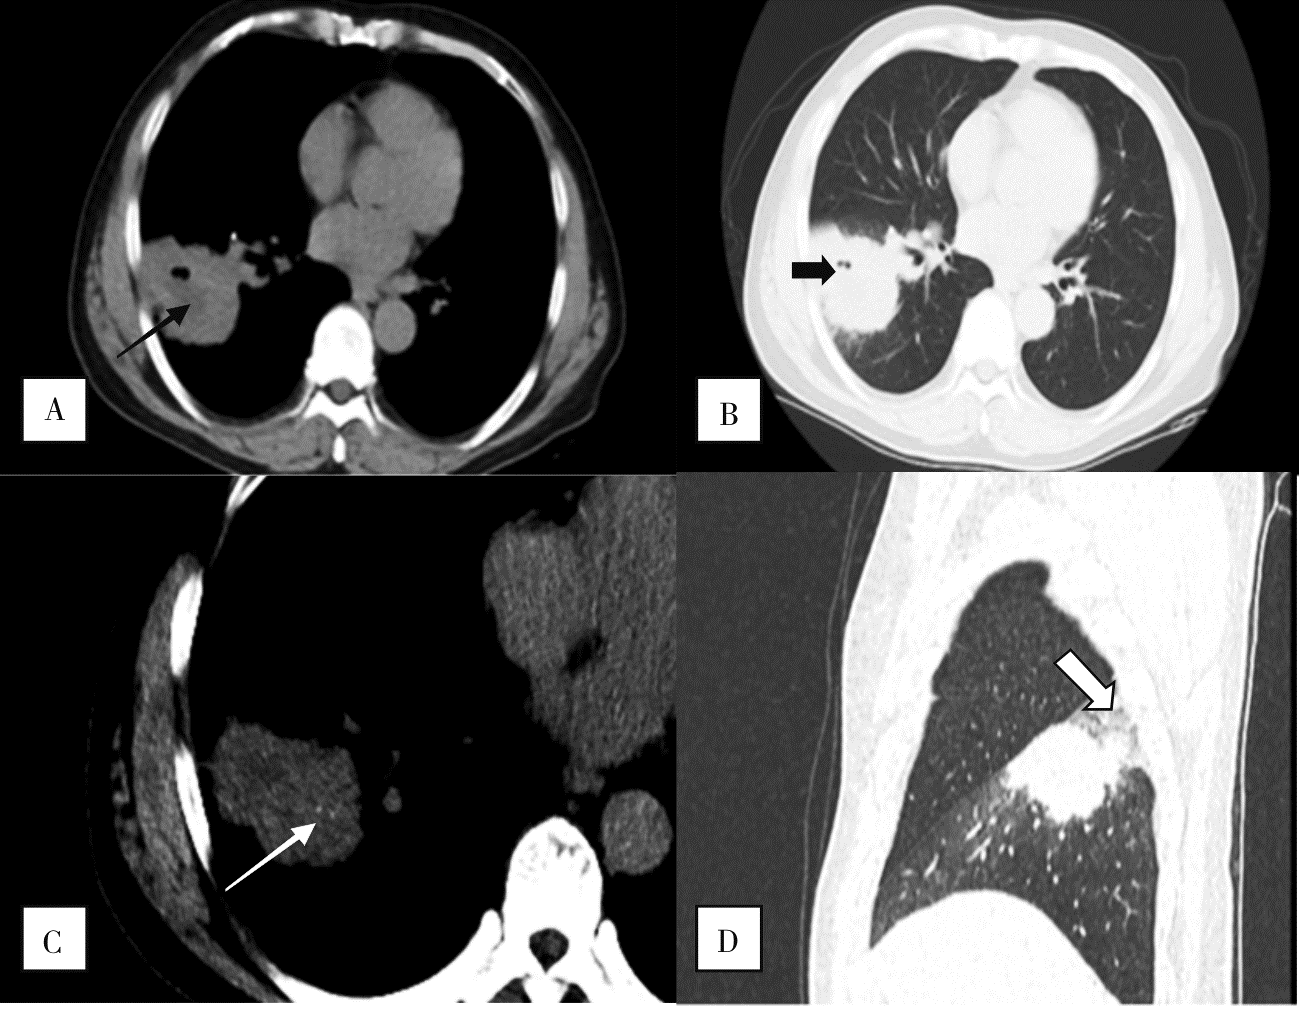

目的:探讨SMARCA4 缺失型非小细胞肺癌(SMARCA4-deficient non-small cell lung cancer, SMARCA4-dNSCLC)的临床与CT影像特征。方法:回顾性收集我院2018年1月至2022年1月期间经组织病理学证实的SMARCA4-dNSCLC患者,以同期收治SMARCA4表达完整的非小细胞肺癌(SMARCA4-intact non-small cell lung cancer, SMARCA4-iNSCLC)患者作为对照组。观察并记录SMARCA4-dNSCLC的临床资料与CT表现,并与SMARCA4-iNSCLC组比较。结果:共纳入SMARCA4-dNSCLC组42例,SMARCA4-iNSCLC组43例。SMARCA4-dNSCLC组男性、吸烟者及患慢性阻塞性肺疾病者比例更高。SMARCA4-dNSCLC组较SMARCA4-iNSCLC组更易出现上腔静脉综合征,而SMARCA4-idNSCLC组更常见咯血。CT表现上,SMARCA4-dNSCLC组肿瘤密度相对更均匀,囊变、坏死及钙化更少见,边界更模糊,且伴发阻塞性肺炎/肺不张比例较低。结论:SMARCA4-dNSCLC多见于老年男性,重度吸烟者,常伴有慢性阻塞性肺疾病。病灶好发于两肺上叶。CT多表现为密度相对均匀的软组织占位,边界不清,无囊变或坏死,罕见钙化。增强后不均匀强化。纵隔淋巴结转移常见。具备上述临床与CT特征者应警惕这一独特亚型的可能。

2组患者的CT特征比较[$\bar{x} \pm s$/n(%)]

| CT特征 | SMARCA4-dNSCLC组(n=42) | SMARCA4-iNSCLC组(n=43) | t/χ2 | P |

|---|---|---|---|---|

| 肿瘤位置 | 3.54 | 0.470 | ||

| 左肺上叶 | 14(33.33) | 12(27.91) | ||

| 左肺下叶 | 6(14.29) | 7(16.28) | ||

| 右肺上叶 | 17(40.48) | 15(34.88) | ||

| 右肺中叶 | 0(0) | 3(6.98) | ||

| 右肺下叶 | 5(11.90) | 6(13.95) | ||

| 肿瘤大小(mm) | 44.0±21.2 | 44.0±22.6 | 0.064 | 0.950 |

| 肿瘤密度[n (%)] | ||||

| 不均匀 | 17(40.48) | 35(81.40) | 14.73 | <0.00 1 |

| 均匀 | 25(59.52) | 8(18.60) | 15.23 | <0.010 |

| 病灶边缘不清晰/毛糙[n (%)] | 42(100.00) | 39(90.70) | 4.03 | 0.045 |

| 病灶囊变/坏死[n (%)] | 0(0) | 7(16.28) | 6.57 | 0.010 |

| 病灶钙化[n (%)] | 2(4.76) | 9(20.93) | 4.73 | 0.030 |

| 强化均匀度[n (%)] | ||||

| 不均匀 | 30(93.75) | 38(88.37) | 0.12 | 0.730 |

| 均匀 | 2(6.25) | 5(11.63) | 1.58 | 0.208 |

| 包绕血管[n (%)] | 9(21.43) | 10(23.26) | 0.09 | 0.760 |

| 累及食管[n (%)] | 3(7.14) | 1(2.33) | 1.07 | 0.300 |

| COPD[n (%)] | 11(26.19) | 23(53.49) | 6.53 | 0.010 |

| 肺不张[n (%)] | 10(23.81) | 19(44.19) | 4.73 | 0.030 |

| 纵隔淋巴结转移[n (%)] | 27(64.29) | 23(53.49) | 1.17 | 0.280 |

| 胸腔积液[n (%)] | 13(30.95) | 14(32.56) | 0.03 | 0.860 |